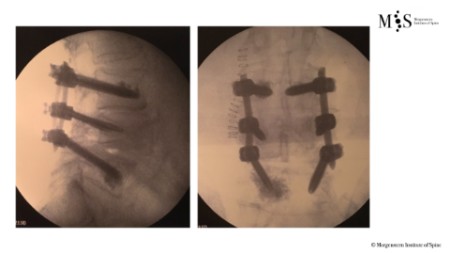

Estabilización percutánea de fracturas vertebrales inestables

En casos de fracturas vertebrales complejas, inestables, conminutas, etc. se requiere una estabilización adicional de la fractura mediante una artrodesis percutánea, y en algunos casos en los que hay compromiso neurológico, una descompresión del canal medular. La artrodesis percutánea permite estabilizar la estrctura comprometida de la columna vertebral y descargar la carga del paciente sobre la fractura. Adicionalmente se suelen cementar las vertebras artrodesas y la fractura vertebral mediante cifoplastia.

Caso clínico con estabilización percutánea de fractura vertebral inestable.